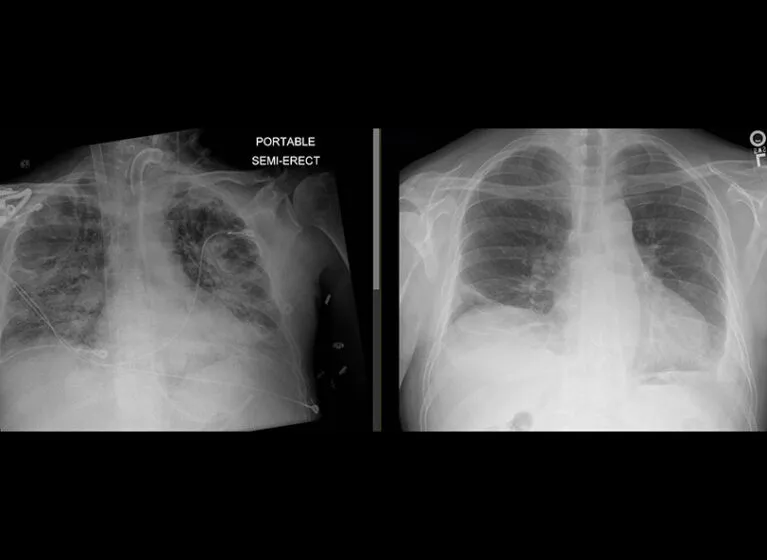

- Clear CXR; no aspiration/trauma

- Imaging: Chest X-ray, CT scans as indicated.

- Primary Graft Dysfunction (PGD): Acute lung injury within 72 hours post-transplant; graded 0-3.